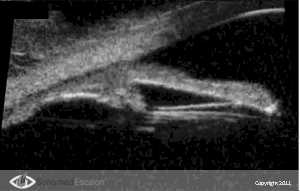

Ультразвуковой биомикроскоп VuMAX® включает в себя очень важную функцию пред- и послеоперационной диагностики при имплантации ИОЛ. Можно совершенно отчетливо увидеть и оценить такие факторы и параметры, как расстояние “sulcus-to-sulcus”, толщина хрусталика, анатомия борозды, форма и размеры цилиарного тела, а также другие анатомические характеристики. Данные параметры очень важны и полезны при выборе типа, дизайна и оптической силы ИОЛ.

При послеоперационной диагностике VuMAX® позволяет хирургу наглядно представить позицию ИОЛ и ее взаимодействие с различными структурами переднего отрезка. Появление имплантируемых контактных линз (?КЛ), ставшее очень хорошей альтернативой для некоторых пациентов, дает превосходные результаты при правильном их расположении. VuMAX® обеспечивает точные и правильные измерения “борозда – борозда” и/или “угол – угол” (в зависимости от типа имплантируемой ?КЛ).

При послеоперационной диагностике с помощью VuMAX® хирург может получить ряд очень важных данных, которые недоступны без использования высокочастотной ультразвуковой биомикроскопии. Совершенно четко на эхограмме можно проследить следующие параметры: правильно ли расположены опорные элементы линзы, расположена ли она по центру и нет ли контакта имплантированной линзы с нежелательными структурами.